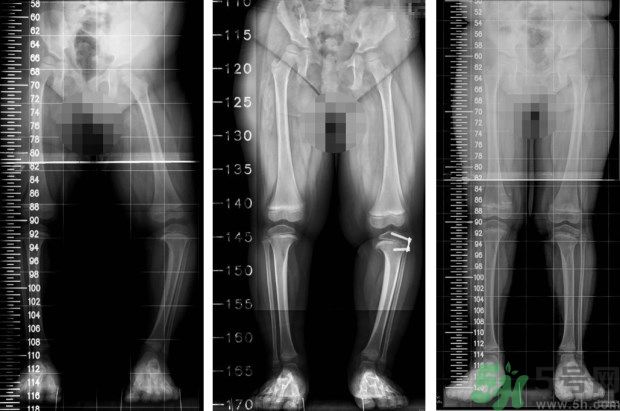

左圖:矯正前,4歲女童,左小腿外側(cè)的生長(zhǎng)板過(guò)度發(fā)育,導(dǎo)致左腳O型腿;中圖:矯正中,在左小腿外側(cè)的生長(zhǎng)板,夾上小夾子,矯正過(guò)度發(fā)育的生長(zhǎng)板;右圖:矯正後,經(jīng)過(guò)1年的生長(zhǎng)板導(dǎo)引治療,恢復(fù)正常的外觀。(照片提供:王廷明 醫(yī)師)